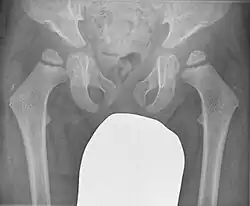

Der klinische Verdacht aufgrund des dysproportionalen Kleinwuchses mit kurzem Rumpf und gelenknahen Verformungen der Extremitäten wird durch die Veränderungen im Röntgenbild bestätigt:

- Höhengeminderte deformierte Wirbelkörper

- Verbreiterung und Deformierung der Epiphysen bei normalen Diaphysen der langen Röhrenknochen